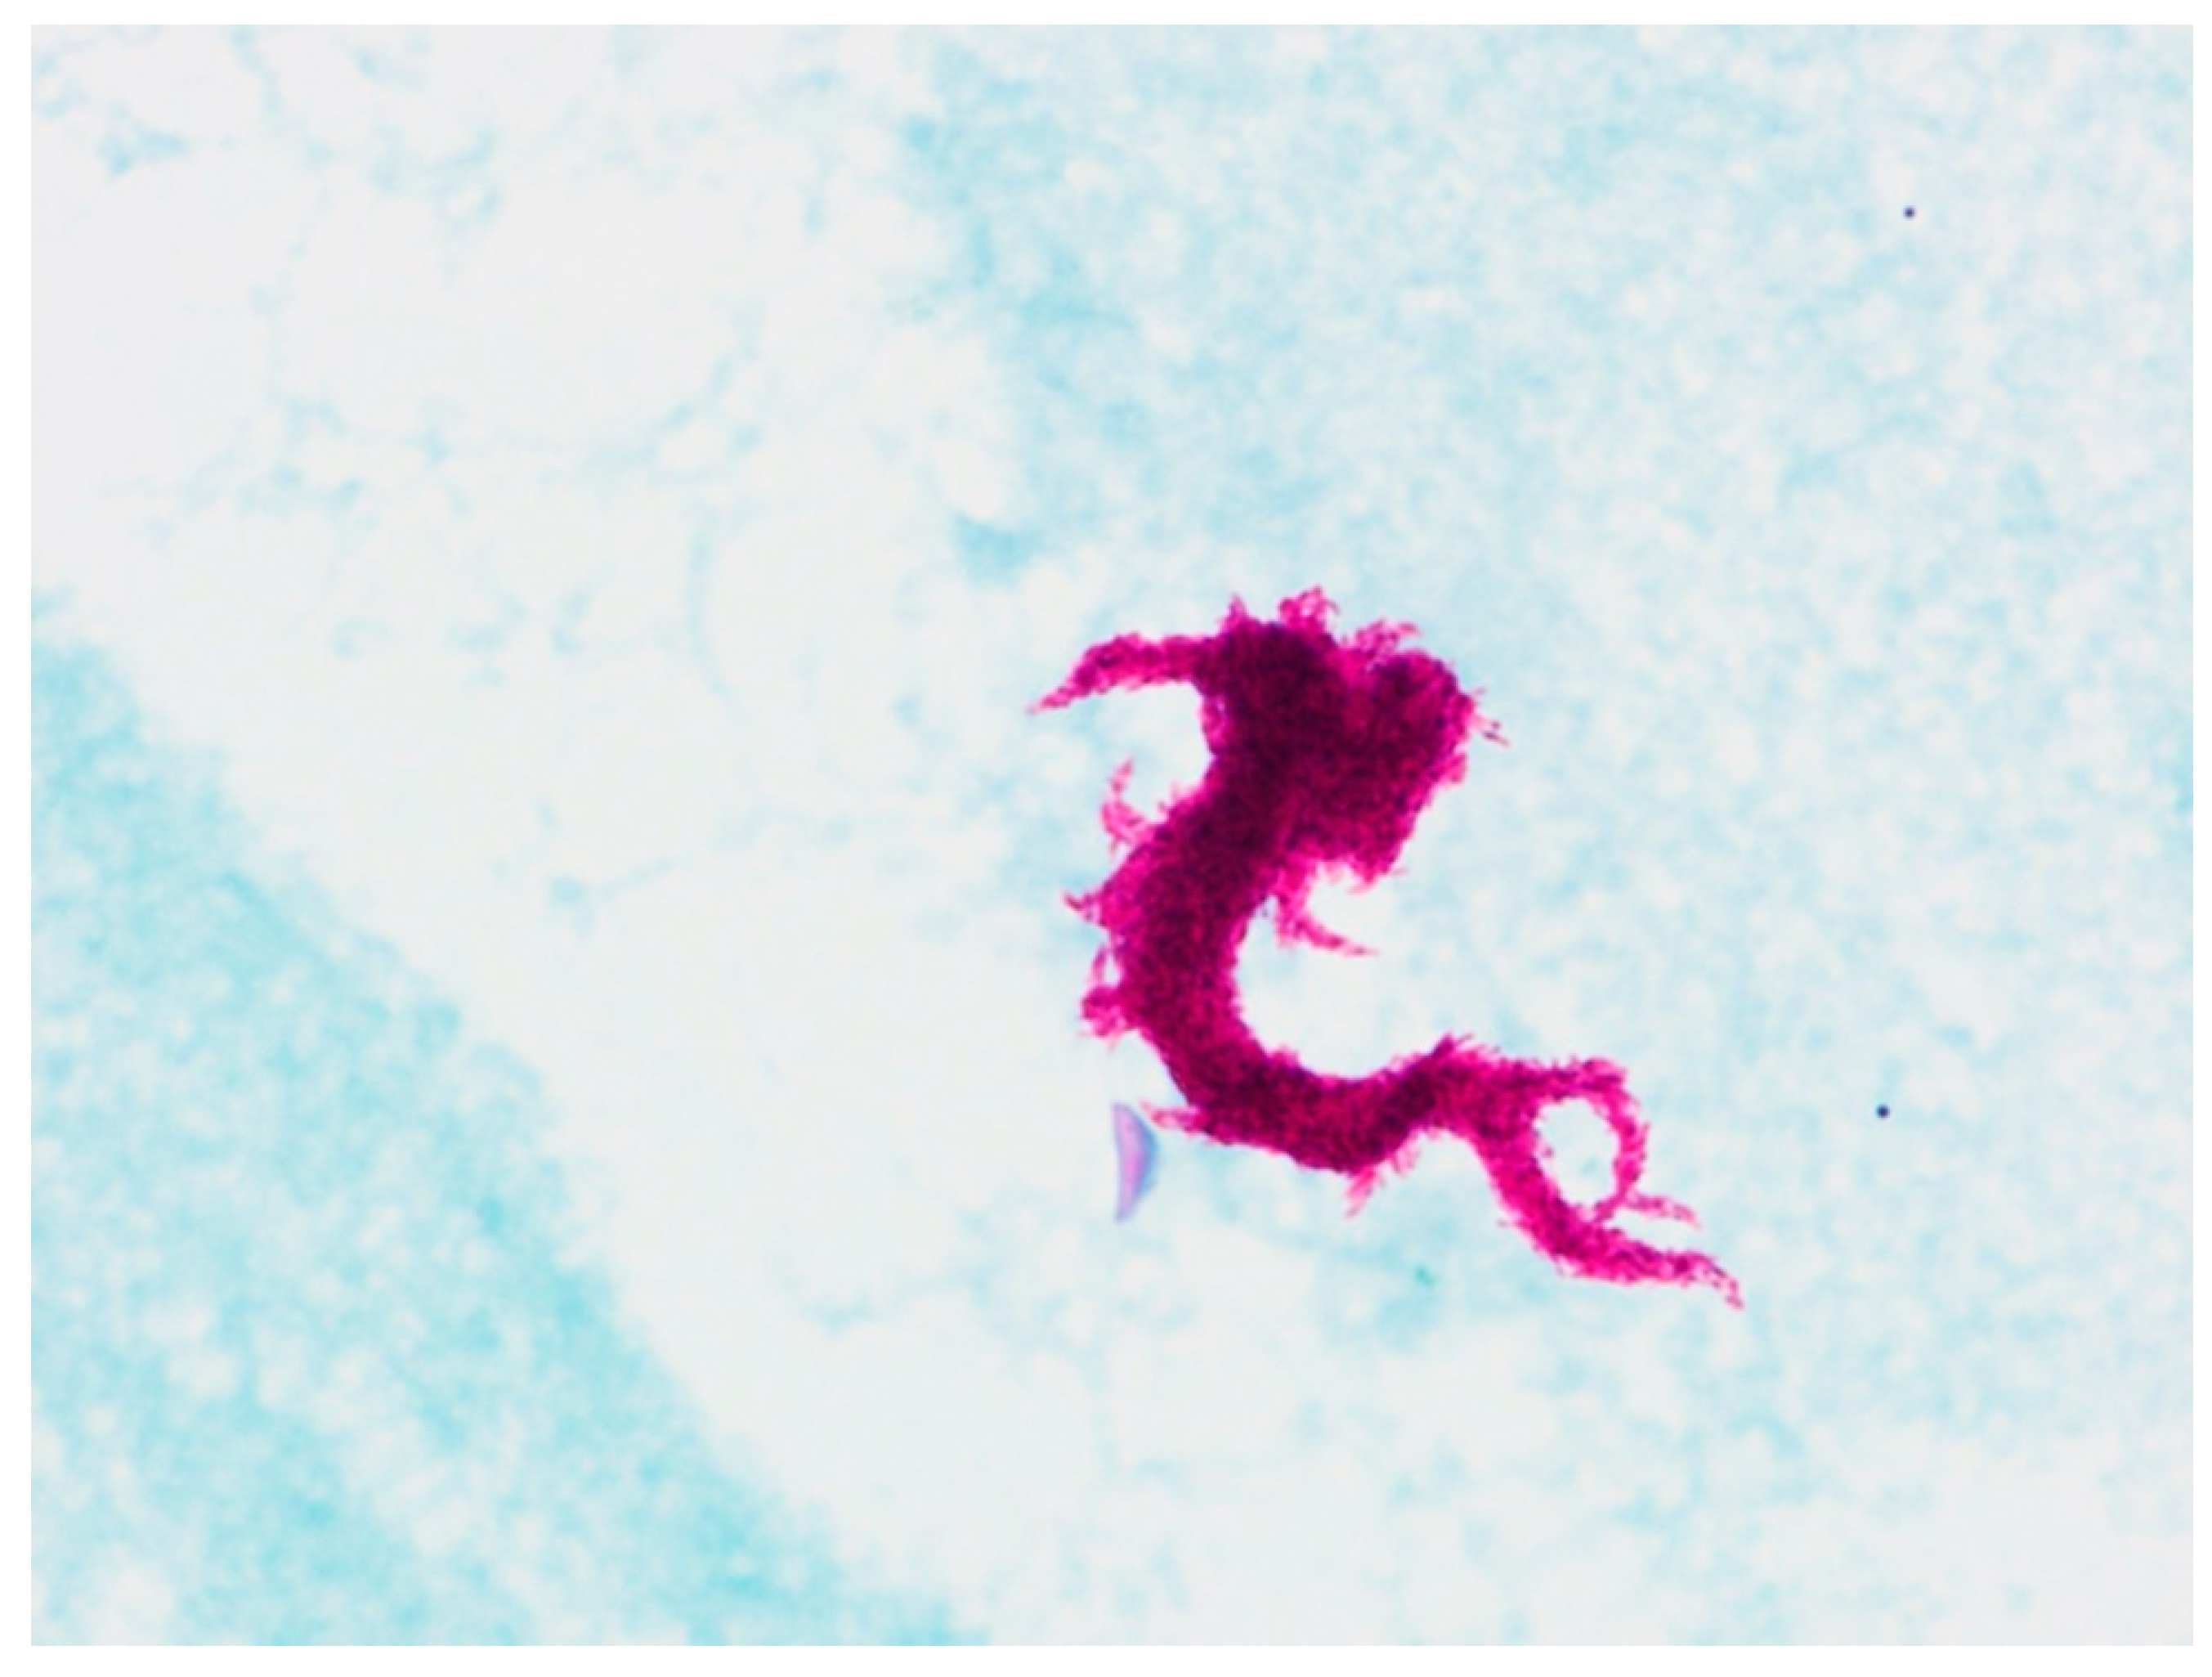

Isolates of mycobacterial cultures on Mycobacteria Grow Indicator Tube (MGIT, Becton, Dickinson and Co., Sparks, NV, USA) liquid media were not producing MPT64 protein in the immunochromatographic test (Becton, Dickinson and Co., Sparks, NV, USA), indicating the presence of NTM in the patient’s samples. However, stains of isolated cultures showed the serpentine cord formation, characteristic of MTBC [14] (Figure 3).

Figure 3. Ziehl-Nielsen-stained slide of mycobacterial cultures obtained on MGIT liquid media with characteristic serpentine cord factor (trehalose 6,6′-dimicolate).